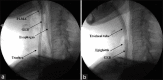

Tracheal intubation is challenging in patients with severe cervical spine pathology. In such cases, awake fiberoptic intubation is the gold standard and safest option for tracheal intubation. However, this technique requires the patient's understanding and cooperation, and therefore, may be contraindicated in patients with refusal or poor tolerance. Herein, we report successful orotracheal intubation in a patient with limited mouth opening and severe cervical spine rigidity under general anesthesia using an extraglottic airway device and a gum-elastic bougie under C-arm fluoroscopic guidance.